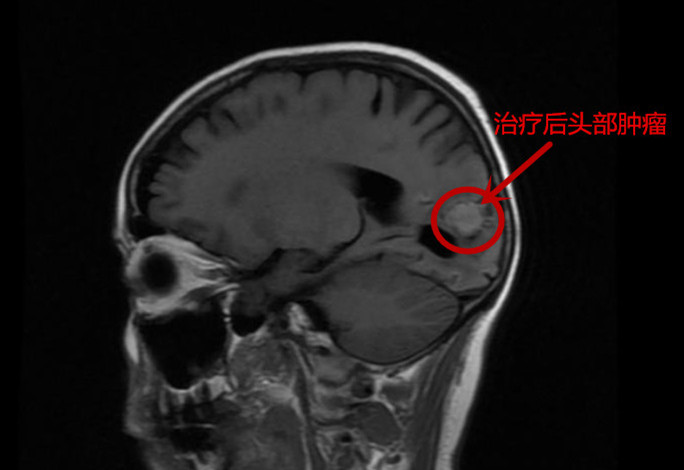

经过一段时间的治疗,张英病情稳定,医生建议可以出院在家服药治疗,但需定期复诊。6月9日患者顺利出院。在精准治疗满两个多月后,8月初,张英入院复查,经过对肺部、头部以及胸椎等处的影像学检查,结果显示肺部肿块及头部的病灶对比第一次入院时缩小了50%以上,胸9椎体的骨质破坏也得到了控制。得知结果后,她激动地对医护人员说:“感谢捷克论坛 肿瘤二科给了我第二次生命,也希望有同样遭遇的病友通过他们的宣传,能重获新生!”